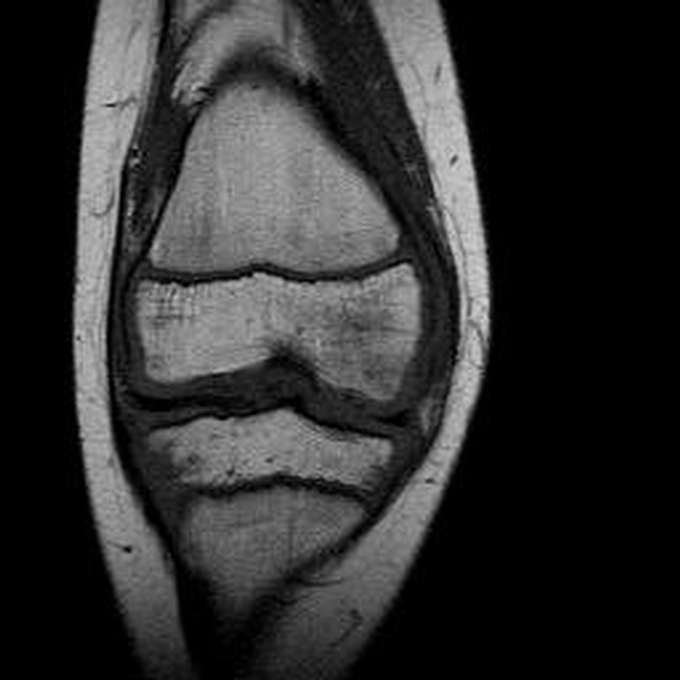

Haemophiliearthropathie bei Haemophilie A.

Arthropathia ARC123 Haemophiliearthropathie bei Haemophilie A.

MRT (high)